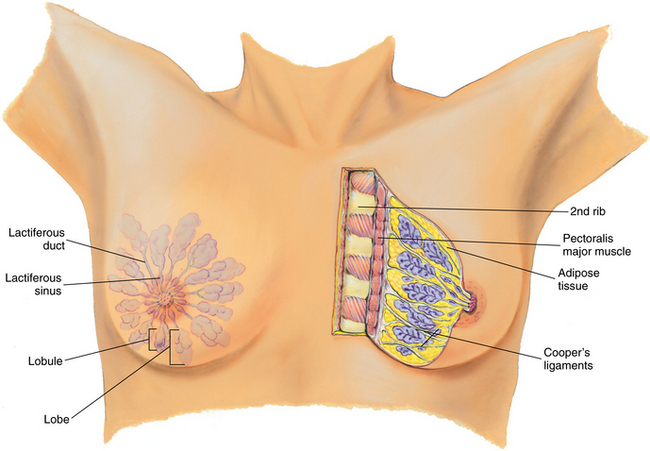

Breast cancer is the most common malignancy of females in the United States and accounts for one-third of all cancers diagnosed in American women. Breast cancer begins in the lobules (20%), which are the milkproducing glands of the breast, or in the ducts (80%), which bring the milk to the nipple (Fig. 20-11). Most breast carcinomas are adenocarcinomas originating in the single layer of epithelial cells that line the ductal and lobular systems of all milk ducts.

Figure 20-11 Breast anatomy. The breast is composed of glandular tissue; fibrous tissue, including suspensory ligaments; and adipose tissue. Glandular tissue contains 15 to 20 lobes radiating from the nipple and composed of lobules. Within each lobe are clusters of alveoli that produce milk. Each lobe is embedded in adipose tissue and empties into a lactiferous duct. There are 15 to 20 lactiferous ducts that form a collecting duct system converging toward the nipple. These ducts form ampullae or lactiferous sinuses behind the nipple, which are reservoirs for storing milk. The lobules and ducts are surrounded by fatty and connective tissue, nerves, blood vessels, and lymphatic vessels. The suspensory ligaments (Cooper’s ligaments) are fibrous bands extending vertically from the surface attaching to the chest wall muscle. These support the breast tissue and become contracted in cancer of the breast, producing pits or dimples in the overlying skin. (From Jarvis C: Physical examination and health assessment, ed 4, Philadelphia, 2004, WB Saunders.)